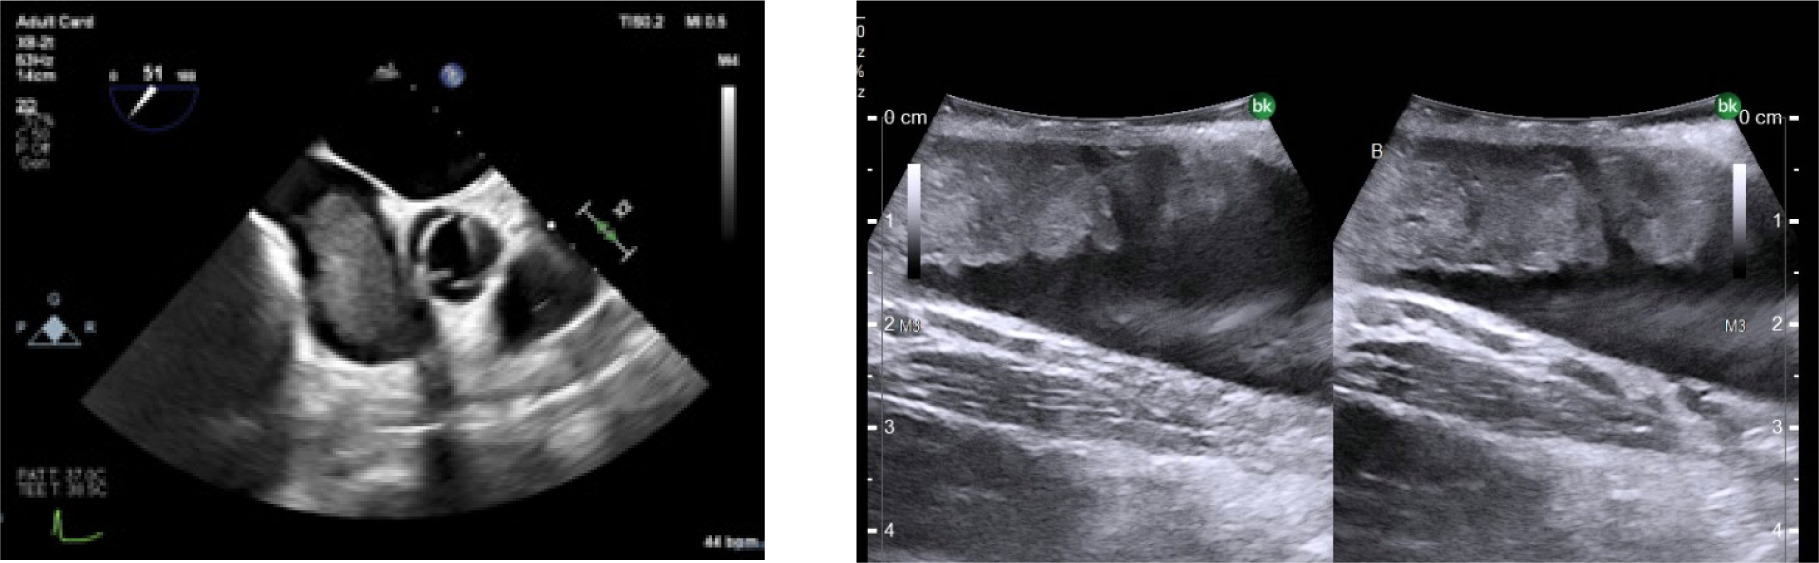

Transesophageal echocardiography (TEE) at the beginning of the operative procedure showed normal heart function with no RV dilation or evidence of emboli. TEE access was maintained throughout the case.

After IVC control was obtained, attempts were made to ligate the right renal artery in the interaortocaval space (5). There was some difficulty visualizing the right renal artery due to tumor-related desmoplastic reaction and the patient’s obesity. During this dissection, the patient became hypotensive with systolic pressures in the 70s. This prompted the urologic surgeon (SD) to request TEE review, which revealed tumor thrombus filling most of the right atrium (Figure 3).

Figure 3: Intraoperative TEE showing tumor thrombus in the right atrium.

As the procedure above was completed, multidisciplinary assistance had arrived including cardiac surgery, interventional radiology, and multiple cardiac anesthesiologists. TEE showed significant intracardiac tumor thrombus now obstructing the right ventricular outflow and hemodynamic instability was worsening. Options for management were discussed including cardiopulmonary bypass (CPB) and embolectomy vs. endovascular extraction. Given the instability, thrombus size, and operating room location, it was felt that survival was most likely with CPB and embolectomy. A conference was held with the patient’s family and the surgical team to confirm that this would be within the patient’s goals of care.

The patient underwent a median sternotomy, providing good exposure of the thoracic cavity. As the pericardium was opened, it became evident that the tumor had traversed into the pulmonary artery by this point. Once CPB was established, a longitudinal incision was made in the main pulmonary artery, and further extended into the left pulmonary artery, allowing excellent exposure of the tumor thrombus. Due to the substantial size of the tumor, it could not be extracted as a single specimen. Therefore, it was removed partially in a morcellated fashion, allowing for complete removal, while preserving integrity of the surrounding structures. There was no visual evidence of remaining embolus in the main, right or left pulmonary artery following pulmonary artery embolectomy. CPB was weaned without significant difficulty and TEE showed good biventricular function with no sonographic evidence of remaining tumor embolus. The sternotomy was closed, and the patient was transferred to the cardiovascular intensive care unit.